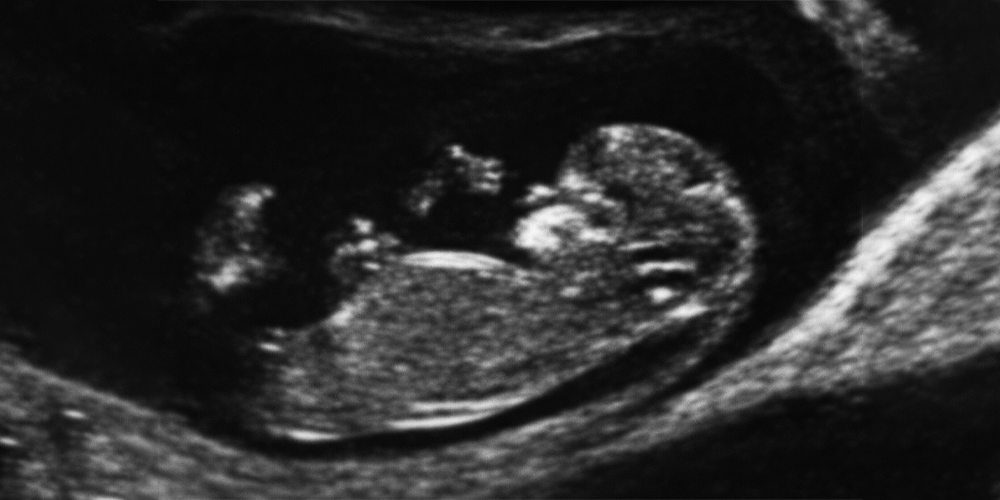

Bu haftaya kadar gelebilmiş olan gebeliklerde ilk anomali muayenesi yapılır. Bu büyüklükteki bir bebekte saptanabilecek ağır anomaliler mevcuttur. Örneğin beyin dokusunun hiç oluşmamaış olması, veya kafatası oluşmadığı için beyin dokusunun açıkta kalması gibi... Veya karın duvarının açık kalıp barsakların karın dışına taşması, bacakların gelişmeyip yapışık kalması gibi...

Çünkü, bu aşamada yapılacak, ikili test, ense saydamlığı ölçümü, burun kemiğinin görülüp görülememesi, barsakların parlak görülmesi, vb. gibi bulguların dedektif gibi araştırılmasının altındaki ana neden bu... Tıbbi davalardaki ana kabul de bu... Yani Down Sendrom'lu bir bebek doğarsa, bunun bir "malpraktis" yani tıbbi kötü uygulama olarak kabulünün altındaki ana kabul: "Kimse Down Sendrom'lu bebek istemez (mi acaba?). Bu konuda her doktor şüphe çekebilecek her türlü ipucunu bulur, şüpheli her hastaya ileri tetkikleri ve amniyosentez gibi tetkikleri yaparak Down Sendrom'lu bebekleri yakalamak ve düşük yaptırmak zorundadır (mı acaba?). Her anne baba da bu Down Sendrom'lu bebeklerinin doğmasına engel olur, ya da başka bir söyleyişle düşük yapılmasını ister (mi acaba?)."